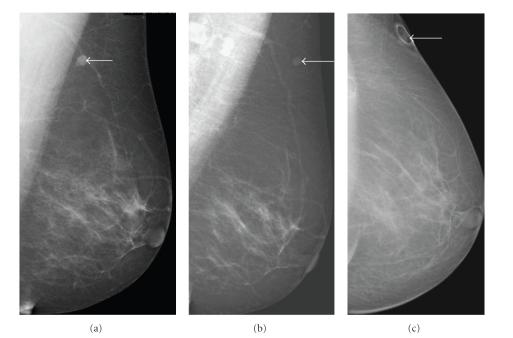

Breast schwannoma.

Schwannomas arise from Schwann cells of the peripheral nerve sheath. The most common locations include the head, neck, and extensor surfaces of the extremities. Intramammary schwannomas are very rare and account for only 2.6% of schwannomas. A review of the English literature reveals 27 such cases of breast schwannoma. In this paper we describe another such rare case.